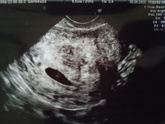

Поздним вечером только открыла почту, а там - результаты пачки анализов, что я сдавала в день скрининга. Всё чистенько, над цифрами гормонов и рисков, конечно, понервничала какое-то время. Давно так сердце не выпрыгивало из груди. От переживаний навернула … Читать далее